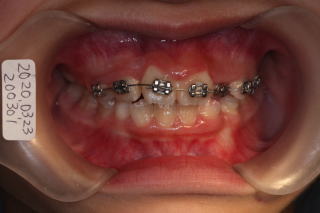

2020年03月16日

反対咬合を改善するため咬合挙上

ブラケットセット、萌出のスペースを確保するために、

オープンコイルセット